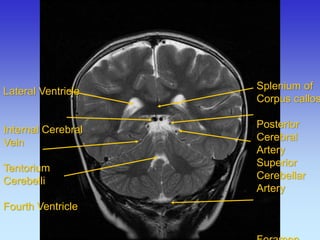

Splenium of Corpus callosum Posterior Cerebral Artery Superior Cerebellar Artery Foramen Lateral Ventricle

Internal Cerebral

Vein

Tentorium

Cerebelli

Fourth Ventricle